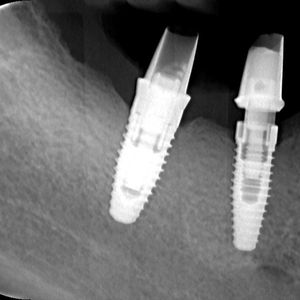

Dental implants are titanium screws surgically placed into the jawbone to serve as artificial tooth roots. Crowns, bridges, or dentures are then mounted on them, creating a functional and aesthetic replacement for missing teeth. Titanium is a biocompatible material that fuses with the bone through a process called osseointegration, making the implant a solid anchor for the prosthetic restoration.

Diagnostics and planning: a thorough analysis of the bone, teeth, and soft tissues using digital radiography. Based on the findings, a precise treatment plan is developed with optimal implant positioning.

Osseointegration: a period of 3 to 6 months during which the implant fuses with the bone. In the meantime the patient wears a temporary restoration.